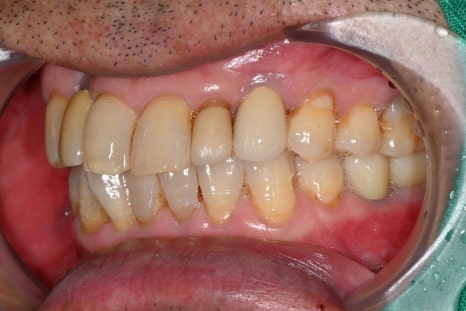

보철 제작과 최종 장착

마지막 단계에서는

환자의 교합에 맞는 보철물을 제작하여 장착합니다.

어금니 임플란트는 씹는 힘을

견뎌야 하기 때문에 정확한

교합 조정이 매우 중요합니다.

임플란트 치과에서는

교합을 여러 번 확인하며 미세 조정을 진행합니다.

치료 후 변화

임플란트는 단순한 치료가 아니라

삶의 질을 회복하는 시술입니다.

치료 후 환자분은

어금니로 음식을 편하게 씹을 수 있게 되었으며,

저작 기능 회복

통증 감소

잇몸 상태 안정

일상생활 개선

등의 변화를 경험하셨습니다.